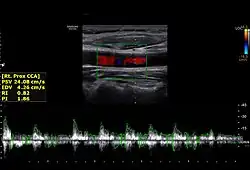

The condition and health of the common carotid arteries is usually evaluated using Doppler ultrasound, CT angiography or phase contrast magnetic resonance imaging (PC-MRI).

Typically, blood flow velocities in the common carotid artery are measured as peak systolic velocity (PSV) and end diastolic velocity (EDV).

In a study of normative men aged 20–29 years, the average PSV was 115 cm/sec and EDV was 32 cm/sec. In men 80 years and older, the average PSV was 88 cm/sec and EDV was 17 cm/sec.[7]